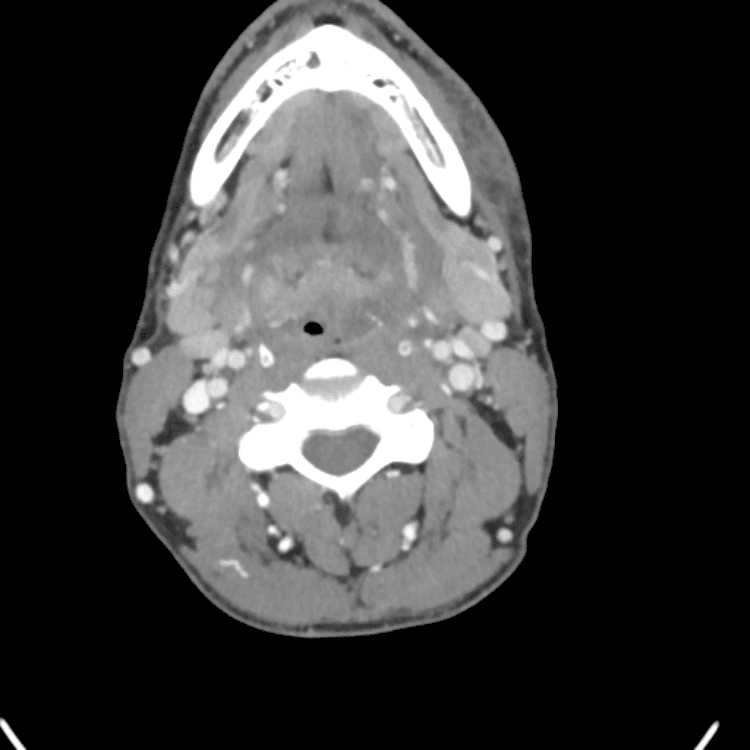

Head and Neck

Practice

Simulates call by including subtle or difficult cases and some normals.

27 cases